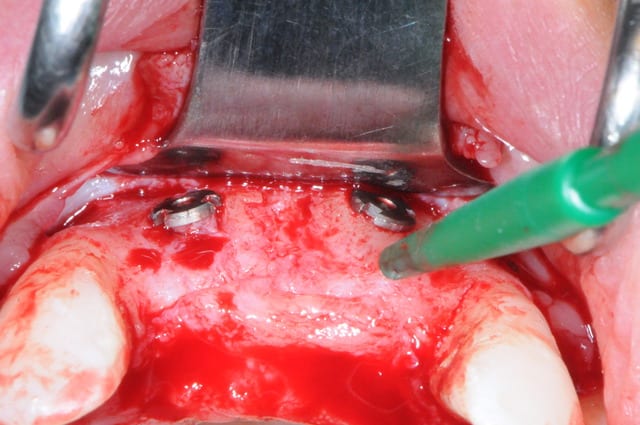

juste pour le plaisir des yeux...

j'étais hier à Strasbourg dans une formation avec Fouad Khoury.

oui biobank et granules de biobank par dessus.

Je trouve que tu ne gagnes rien en épaisseur au niveau de la crête ( mais on ne vois pas bien avec le lambeau , tu as peut être assez ? ).

Pour juste combler les dépressions, tes deux vis en piquets de tente sans bloc auraient fait aussi bien.

Sans membrane collagène sous le PRF , tu ne crains pas de perdre tous tes granules ?